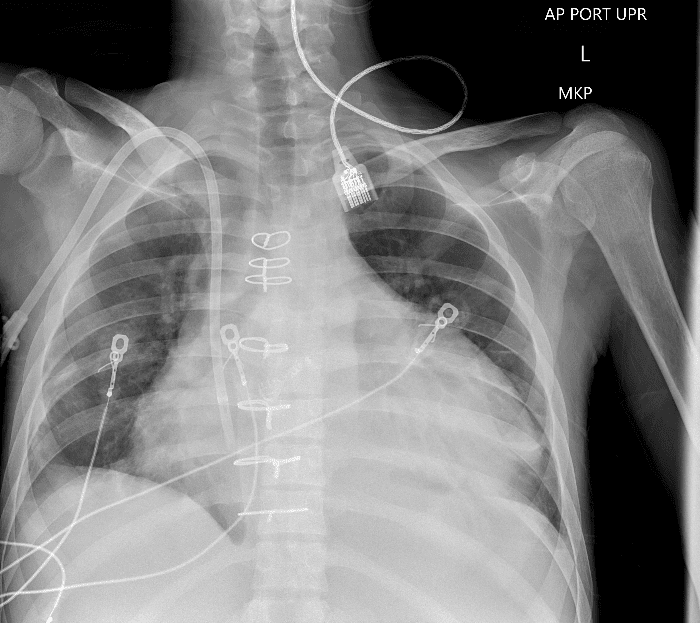

Practice Cases